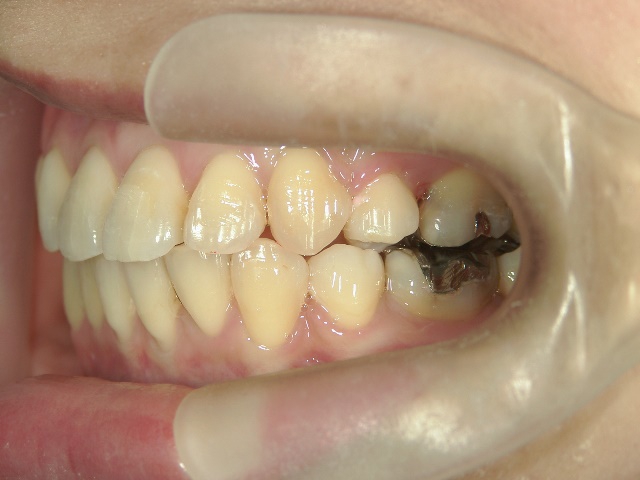

矯正歯科 治療前